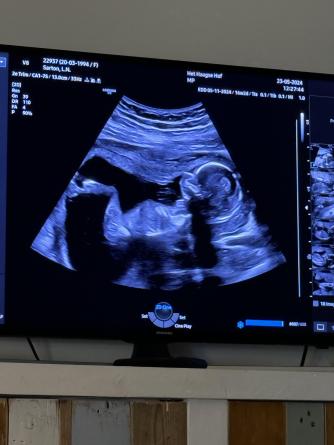

Donderdag 23 mei 2024

Weer op tijd eruit vandaag weer een echo even nog een keer gluren om het zeker te weten wat het gaat worden . Beau mijn nichtje haalt mij om half 12 op . Daniël doet in de tijd dat ik weg ben samen met Jennifer de boodschappen voor de gender reveal 🩵🩷 bij de echo is het geslacht nog steeds hetzelfde gelukkig maar anders konden er een aantal pakjes terug . In de middag pak ik verder de cadeautjes in . Inmiddels een hele tas vol 🎈🎁 ik lig lekker daarna op de bank en kijk tv om half 10 vertrek ik dan eindelijk naar bed . Vandaag een lange dag geweest ik ben kapot maar voldaan. Het was het waard !!!